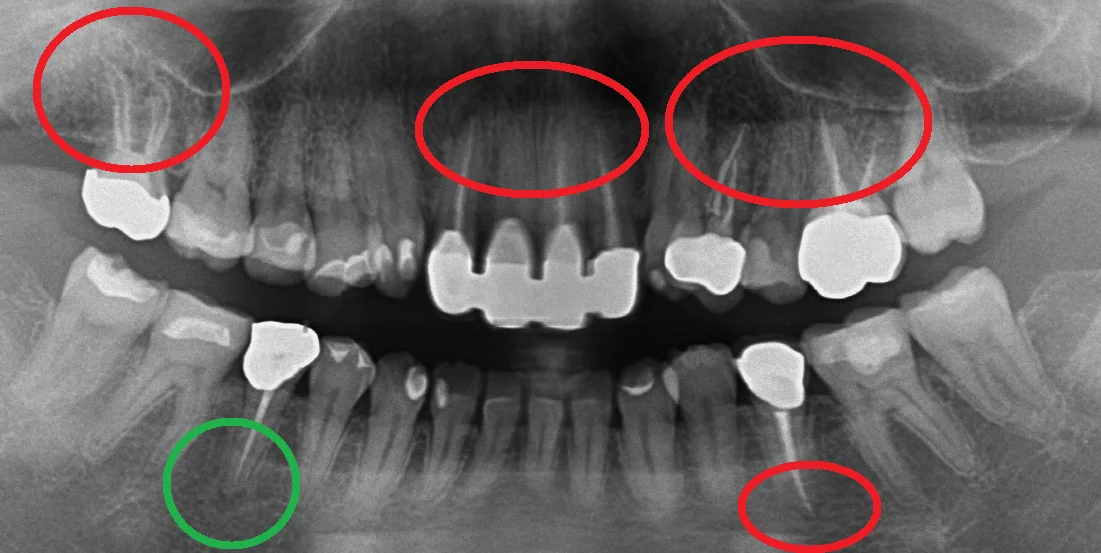

では本題の写真がこちらです。

こちらが術後1年半経過後、初診に戻った際に撮影したものです。

赤丸の部分がすべて私の方で神経の治療を行わせていただいた部分になります。

緑丸の部分が治療を行っていないところですね。

そしてそれら全てで根の先の膿が小さくなっているのがわかります。

本数的に言うと・・・7本ですね。

また治療後の補綴物も全て適合よく入っているので、まったく問題ありません。